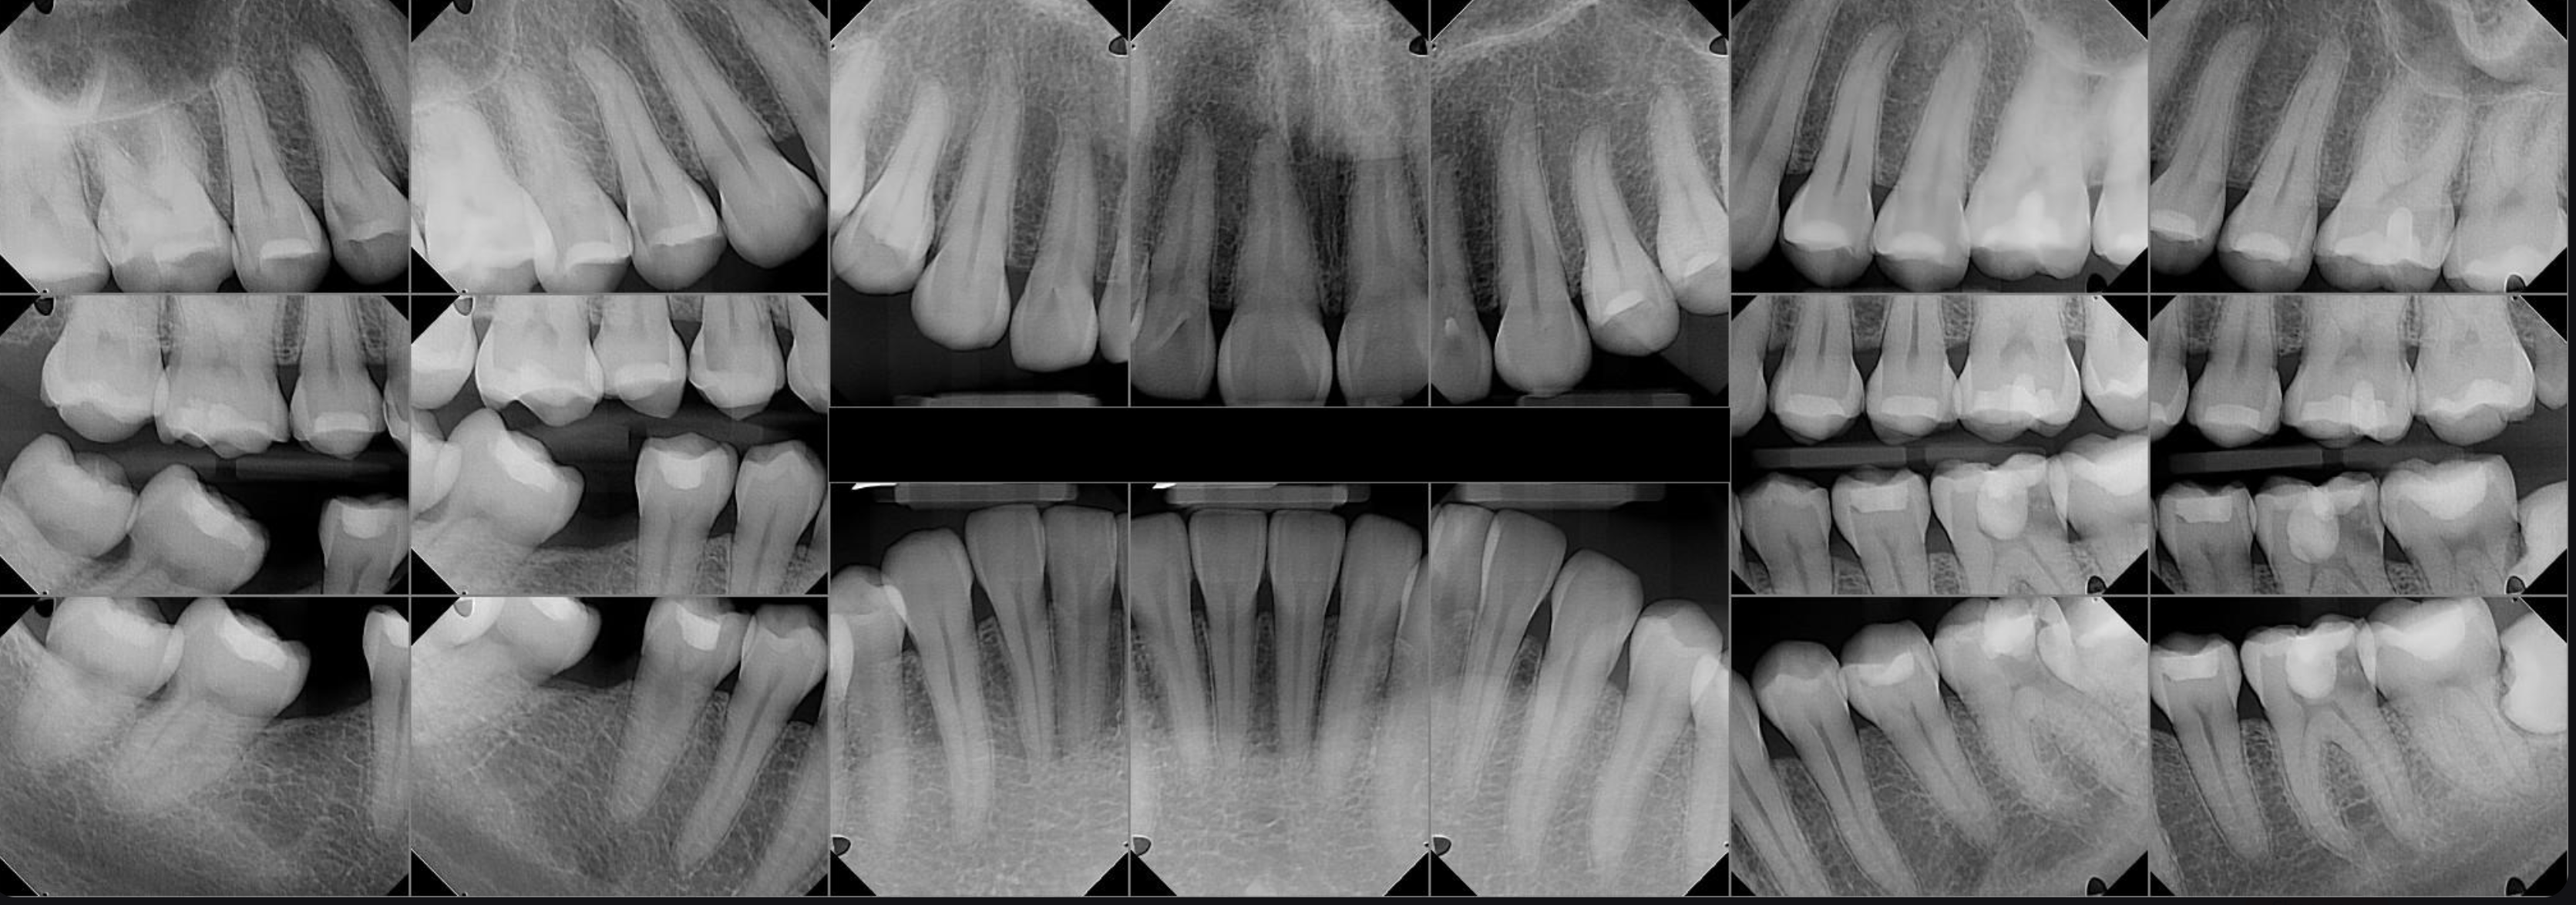

So far, I have had 5 teeth extracted, 3 were wisdom teeth which needed to come out, but 2 were main molars on my right bottom side that dentists could not save because they were too damaged by wisdom teeth that came in. I need these to chew and have a fully operating mouth. If I do not get implants I risk losing my top teeth because they can shift or super-erupt. I also risk bone loss or disfigurement to my jaw. Worst of all, I won't be able to eat or speak properly. I’m young, so a denture is not advised. Right now I’m pretty gummy on that bottom right side and lisping a little bit lol.

On top of this, I had an emergency root canal on my left side that is in need of a crown and before I can get a crown on that tooth I need surgery to shave down the bone. The molar next to that one, the one impacted by the wisdom tooth directly, is going to be sensitive for a while due to bone resorption.

Luckily, I am being treated at a nearby clinic that is affordable but they are cash-up-front before they do any work and I have a limited time frame with my assigned student doctor.

In total I need help with: wisdom tooth extraction surgery + extraction, RCT treatment, jaw surgery, crown, implants + sedation for those.